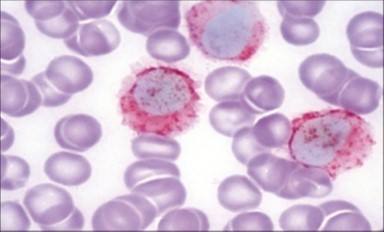

The classic hairy cell is medium sized with a magnitude of 10-14µm. The moderately abundant or variable cytoplasm may be transparent or mildly basophilic. The cellular surface with the characteristic serrated perimeter depicts innumerable fragile or stout extensions of cytoplasm ,particularly discernible on the phase contrast and electron microscopy. The cytoplasm may exhibit vacuoles with occasional azurophilic granules4. The nucleus may be elliptical or reniform, folded or indented with a coarse, reticulated or a finely dispersed chromatin and inconspicuous nucleoli along with infrequent mitosis. Bone marrow aspiration or bone marrow trephine biopsy may be inadequate for diagnosis in 30%-50% individuals4. The trephine sections of the bone marrow may depict a characteristic interstitial pattern of leukaemic infiltration. Generally the bone marrow is hyper-cellular, though it may be hypo-cellular in 10-15% individuals4. The leukaemia cell ingress may be diffuse or partial, although diffuse infiltration is frequent. The partial variety of leukaemic dissemination may be ineptly categorized with an indeterminate differentiation from the uninvolved marrow. The malignant insertions may initially emerge as miniature, undefined, cellular loci. The formalin fixed, paraffin embedded sections may elucidate a crystalline zone or a “halo” appearance of the cells with a circumscribed nucleus on account of the plentiful cytoplasm4. The cellular margins may be intertwined. Fixation of bone marrow smears with Zenker’s fixative may demonstrate a retracted cytoplasm of the hairy cells with a consequent disconnected structure. The bone marrow in the absence of a malignant process may be hypo-cellular or hyper-cellular. Reticulin stains may delineate an enhanced accrual of broad, dense reticulum fibres surrounding the aggregates of leukaemia cells with the fibrous circumlocution of individual malignant cell and fibrotic extensions into the abutting, uninvolved bone marrow4.

The leukaemia cells may enunciate a characteristic immune phenotype, crucial for a confirmatory diagnosis. The peripheral blood mononuclear B cell population may display a kappa or lambda light chain restriction. The phenotype of classic hairy cell leukaemia may be delineated by concurrent, immune reactive CD19+ CD20+,CD 11c+, CD25+, CD103+ and CD123+. An intensely immune reactive CD200+ and a non reactive CD27- antigen may be present2, 4. Evaluation of a trephine bone marrow biopsy and bone marrow aspirate may define the degree of tumour infiltration. A dry tap on account of prominent bone marrow fibrosis may be elucidated at preliminary diagnosis. A decline in the normal haematopoiesis may account for a hypo-cellular marrow in 10% instances. Gradation of cellular infiltrating of the leukaemia within the bone marrow may be appropriately investigated with immune –histochemical stains2, 4. Immune staining for CD20+, annexin 1 and VE1 (a BRAF V600E stain] may validate the diagnosis and precisely analyse the extent of malignant bone marrow infiltration[8]. Determination of BRAF V600E mutation may be critical in therapeutically non responsive individuals with applicable standard therapy or in instances of multitudinous reoccurrences[9]. Deploying inhibitors of BRAF V600E gene may be efficacious in patients impervious to approved therapy. The mutation necessitates a comprehensive scrutiny of the implicated individuals with a sensitive molecular assay which may discern up to < 10% of the hairy leukaemia cells appearing in the peripheral blood smears or bone marrow aspirates diluted with peripheral blood or aspirates elucidating a dry tap[2,4]. Allele specific polymerase chain reaction (PCR) or a next generation sequencing may be optimally employed to circumvent false negative outcomes. If the leukaemia cells are sparse or if particularly sensitive & efficacious molecular techniques are not accessible, the application of appropriate immune histochemical stains to the bone marrow biopsy such as a BRAF V600E mutation stain (VE1) may detect the hairy cells and conclusively diagnose the condition[2,4,10]. Figure 1, Figure 2, Figure 3, Figure 4, Figure 5, Figure 6, Figure 7, Figure 8, Figure 9, Figure 10, Figure 11, Figure 12, Figure 13, Figure 14.

Figure 13.HCL: hairy cells immune reactive for CD 11c(24).

Figure 14.HCL: hairy cells with demonstrable tartrate resistant acidic phosphatise( TRAP) stain(29).